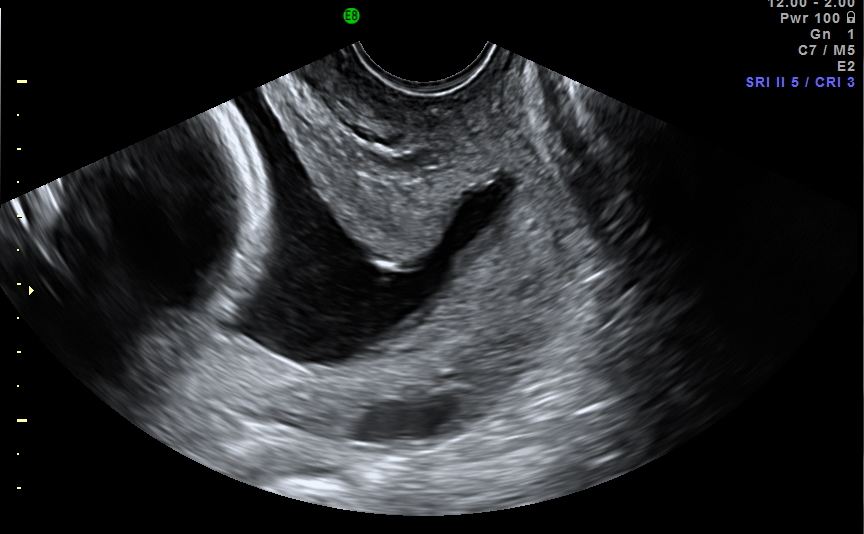

How To Measure Cervical Length On Ultrasound Transabdominal And

Longitudinal view of a short cervix with funneling. The line indicates Short Cervix Length During Labor With respect to treatment of short cervix or preterm labor, 17p has not shown benefit and is not recommended. 86,87,91 weekly injections of 17p are usually discontinued at 36 weeks or. During pregnancy, the cervix gets longer, putting a more. When you’re not pregnant, it’s generally pretty short — about 25 millimeters (mm) on average — and closed. During pregnancy,. Short Cervix Length During Labor.